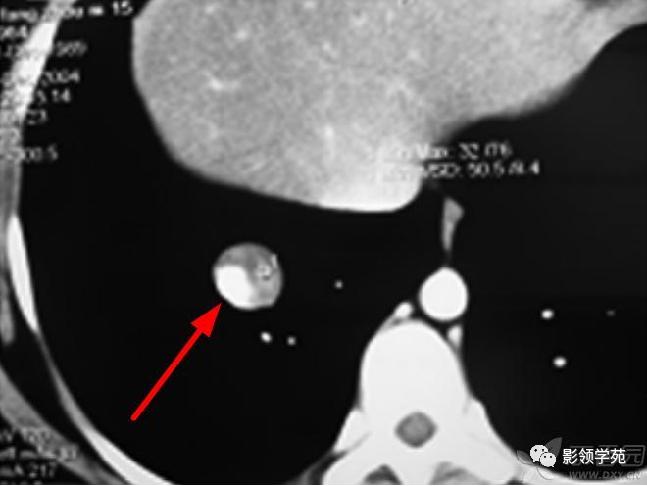

结节或肿块周围可见晕轮征、供养血管征。晕轮征提示肺结节或肿块出血,CT表现为结节或肿块周围磨玻璃密度影;供养血管征CT表现为血管影进入结节或肿块内,提示病变以血管为中心生长。

病例1:双肺多发大小不等结节,右肺中叶结节周围见晕轮征及供养血管征。

病例2:右肺下叶肿块周围见晕轮征